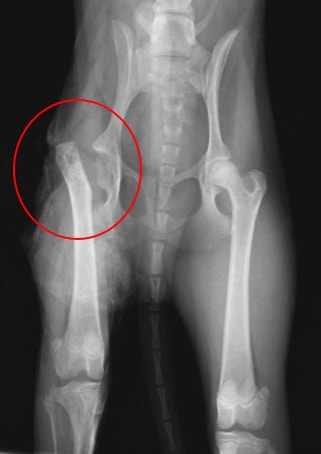

![]() 手術前のレントゲン写真です。  |

診断は、レントゲン検査で行い、大腿骨頭の変形、大腿骨頭のX線透過性領域の増大、大腿骨頚の肥厚、股関節腔の拡張、などが認められます。

大腿骨頭への血液供給源である大腿からの血管が細くなり虚血し、大腿骨頭が壊死する病気です。正常な体重の加重下で大腿骨頭の破壊と変形がみられ、股関節の疼痛を伴い、跛行が起こり、その結果重度の大腿の筋委縮が起こります。